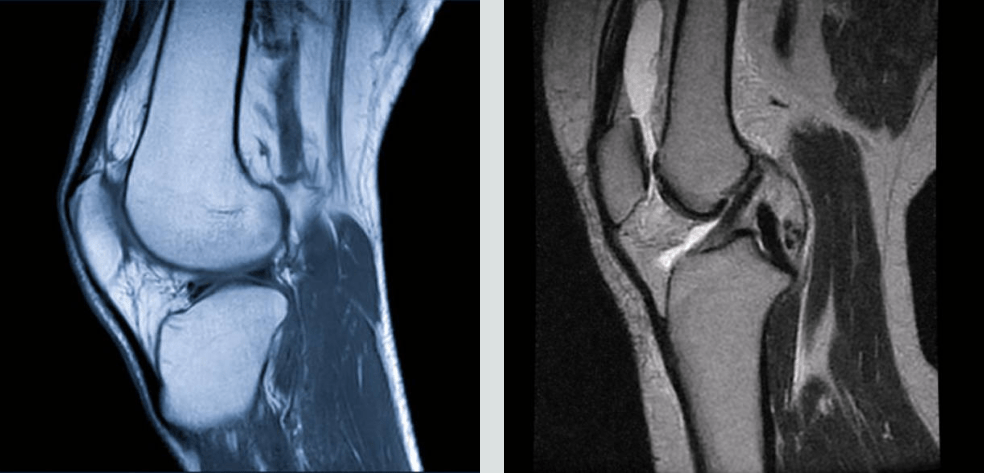

IRM

L’IRM est un examen de référence en orthopédie pour l’analyse fine des tissus mous et des structures internes.

Principales indications :

- Lésions ligamentaires ou méniscales

- Atteintes cartilagineuses

- Pathologies musculaires et tendineuses profondes